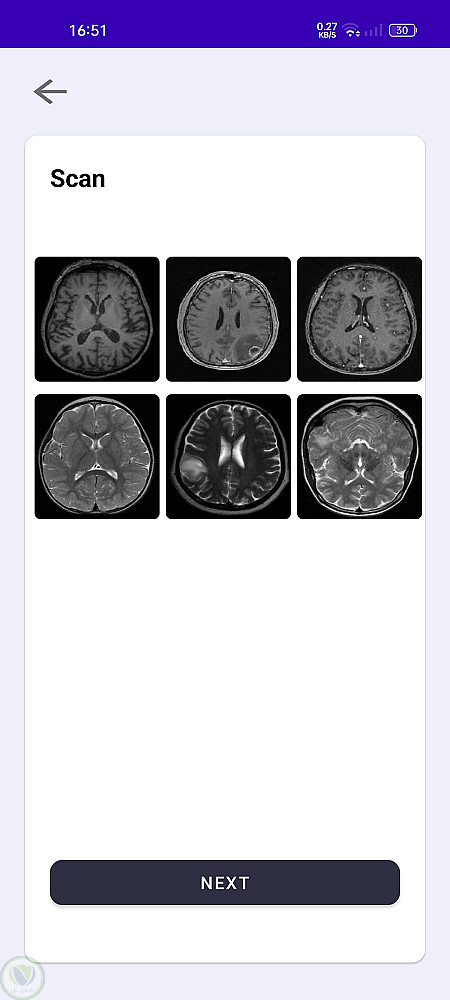

يتيح هذا التطبيق للمستخدمين رفع صور أشعة الرنين المغناطيسي للكشف عن أورام الدماغ باستخدام نماذج تعلم الآلة. يمكن للمستخدمين إدارة بيانات المرضى، والتواصل مع الأطباء عبر الدردشة، وحفظ التقارير للرجوع إليها لاحقًا